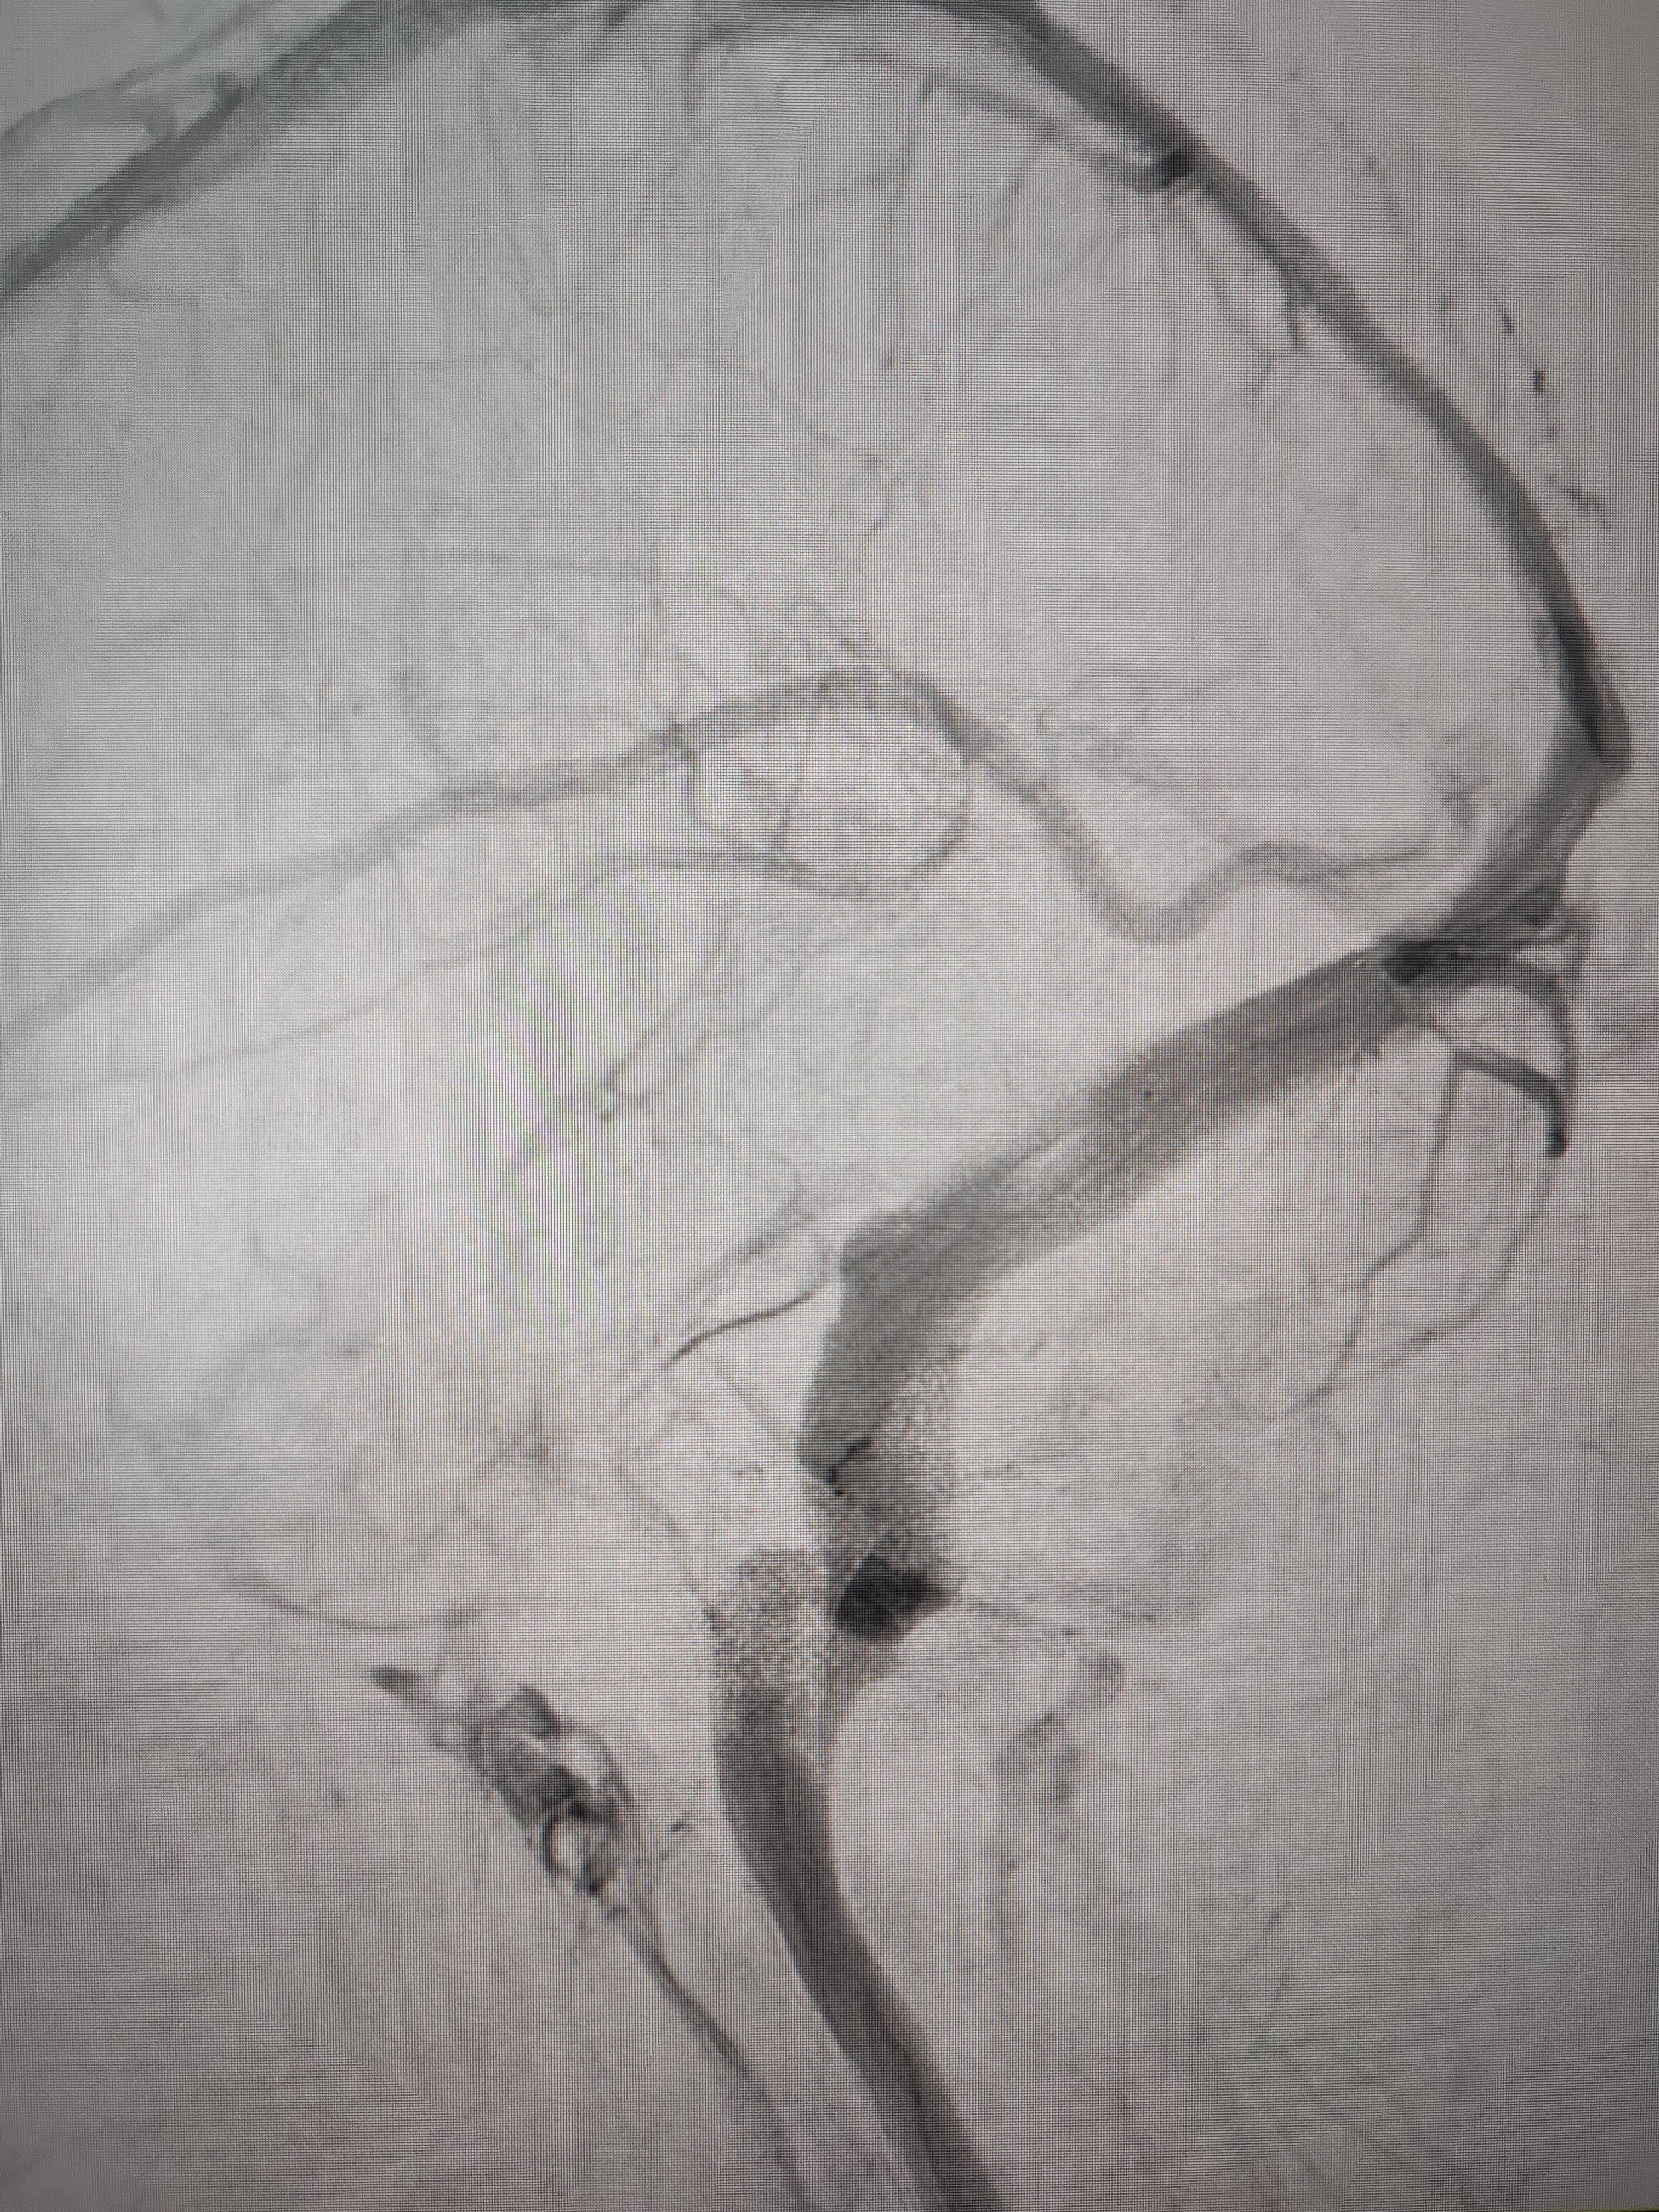

经过静脉窦支架置入手术治疗后,患者的静脉窦“堵点”被打通truechain币行情。 南方+ 欧阳少伟 拍摄

“从手术室出来,麻药清醒以后,我感觉整个世界都清静了,没想到效果这么立竿见影truechain币行情。”减轻病痛的赵女士,术后很是开心,次日就可下床自如活动,目前已康复出院。